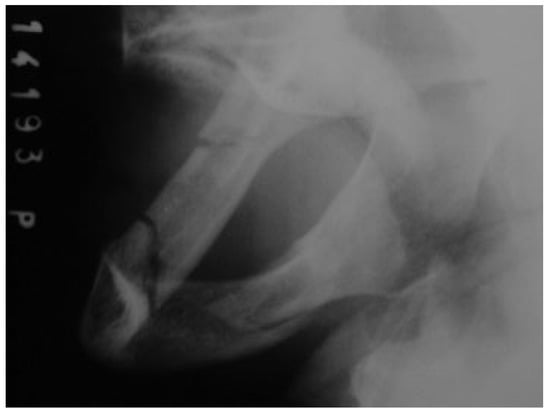

An 81-year-old woman was referred to the University Hospital after a fall. An oral exam and mandibular X-rays (Figure 7 and Figure 8) revealed two fractures of the mandibular bodies, one on each side. The patient presented mouth-opening limitation and bilateral lower-lip paresthesia. According to Luhr et al. [12] classification, the patient presented a class III atrophic mandible and its height at the lowest point was 5 mm.

Figure 7. Preoperative posteroanterior mandibular radiograph.

Figure 8. Preoperative lateral oblique mandibular radiograph.